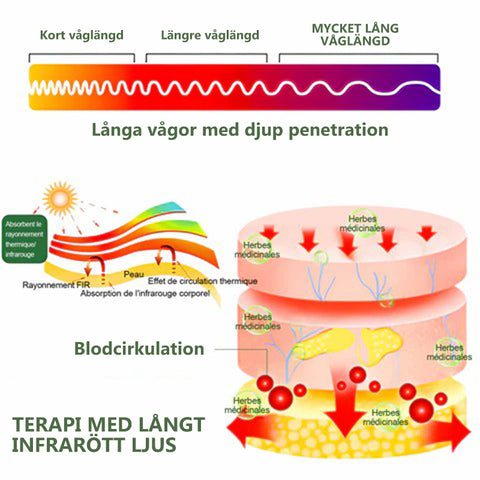

Långt infraröd terapi

Långt infrarött är ett område av det infraröda spektrumet av elektromagnetisk strålning. Långt infraröda strålar kan penetrera 16 mm av mänsklig subkutan vävnad , vilket innebär att de kan passera genom djupa muskelvävnader, senor, nerver, blodkärl och ligament och hjälpa till att reparera skadade celler, förstora mikrokärl, främja blodcirkulationen, aktivera enzymer och påskynda ämnesomsättningen av blod och cellulära vävnader. Det gör den genom att värma upp kroppen och stimulera puls och aktivitet, även när du inte tränar. Det stimulerar också blodflödet, cirkulationen och produktionen av enzymer och hormoner, som är avgörande för fettförbränning och viktminskning.

Forskning har visat att långa silkestrumpor för jonisk korrigering och lymfatisk avgiftning är ett utmärkt val för att behandla knäsmärta och inflammation. långa sidenstrumpor för jonisk korrigering och lymfatisk avgiftning producerar infraröd ljusterapi utan behov av en extern energikälla. Enligt New York Medical Center är det enklaste, säkraste och mest effektiva sättet att behandla de flesta sjukdomar, inklusive cancer, med infraröd ljusterapi. Infraröd ljusterapi främjar vasodilatation, ökar blodflödet, förbättrar cirkulationen och hjälper till att leverera näringsämnen och syre till alla delar av kroppen.